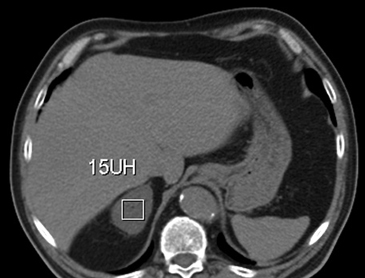

La presencia de lípidos intracelulares disminuye la densidad de la lesión debido a que estos son menos densos que el agua. El primer estudio en reportar la utilidad de la densitometría por TC en la diferenciación de una lesión suprarrenal benigna de una maligna fue el realizado por Lee et al6, utilizando la medición del coeficiente de atenuación o densidad de la lesión expresada en unidades Hounsfield (UH), en una TC no contrastada, demostrando que el coeficiente de atenuación promedio de los adenomas (2,2 UH) fue significativamente menor que la de las lesiones no adenomas (28,9 UH). Utilizando un punto de corte de 0 UH la sensibilidad de la TC no contrastada en la caracterización de un adenoma es cercana a un 47%, con una especificidad de aproximadamente 100% (Figura 9 a y b). Sin embargo, estudios posteriores7 han corroborado que al utilizar un punto de corte de 10 UH, la sensibilidad asciende a un 71%, y la especificidad se mantiene en prácticamente 98%, por lo que este umbral de densidad es el más utilizado en la actualidad. Es importante enfatizar que para una adecuada medición de la densidad, la región de interés (ROI) no debe incluir áreas de necrosis ni de hemorragia, y debe abarcar al menos la mitad o dos tercios de la lesión, para evitar el artefacto por ruido y el efecto de volumen parcial con el tejido adiposo adyacente (Figura 10).

Figura 10. Adenoma suprarrenal derecho. Lesión suprarrenal derecha, cuya densidad es consistente con un adenoma típico. En la imagen se demuestra una adecuada medición de la densidad lesional, con una región de interés (ROI) que abarca al menos dos tercios de ésta.